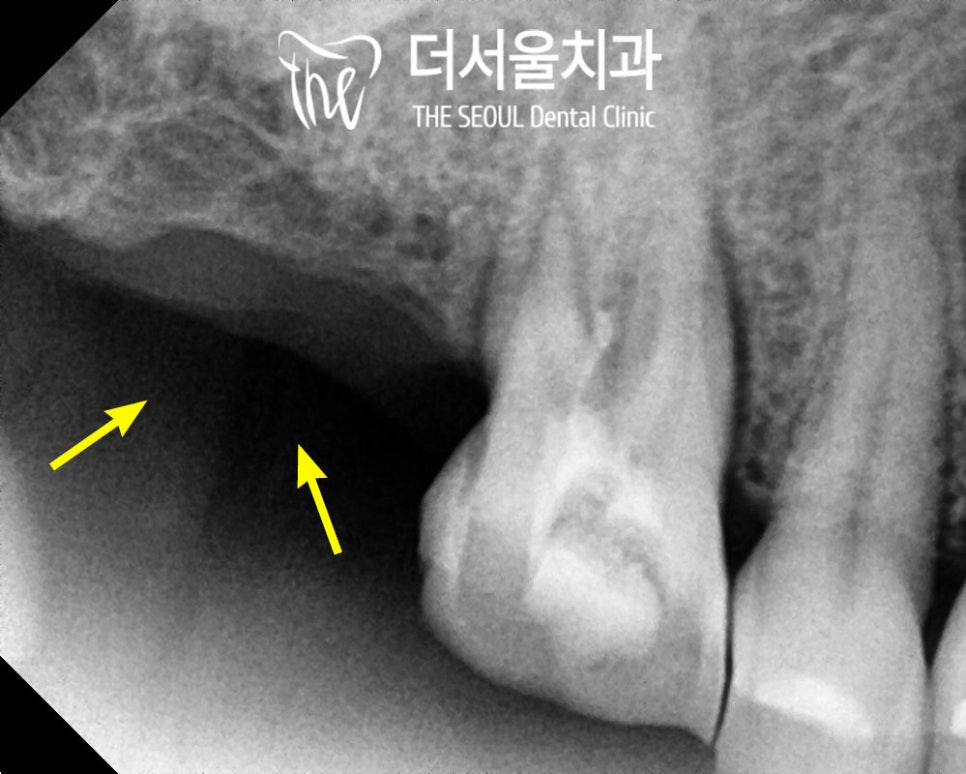

치근단 사진을 촬영해 보았더니

제2대구치가 없기 때문에

제1대구치가 어금니의 씹는 힘을

대부분 받고 있었고,

이로 인해 균열이 발생해

통증을 느끼신 것 같습니다.

사람들 모두 치아에

미세한 잔금은 가지고 있지만

이렇게 찌릿한 느낌이 든다면

이는 미세한 금이

외부 자극으로 인해 벌어지면서

주변의 치주인대가 찢어질 때

느껴지는 통증입니다.

아쉽지만 이럴 경우에는

크라운을 씌워 이를 보호해줘야됩니다..ㅜ